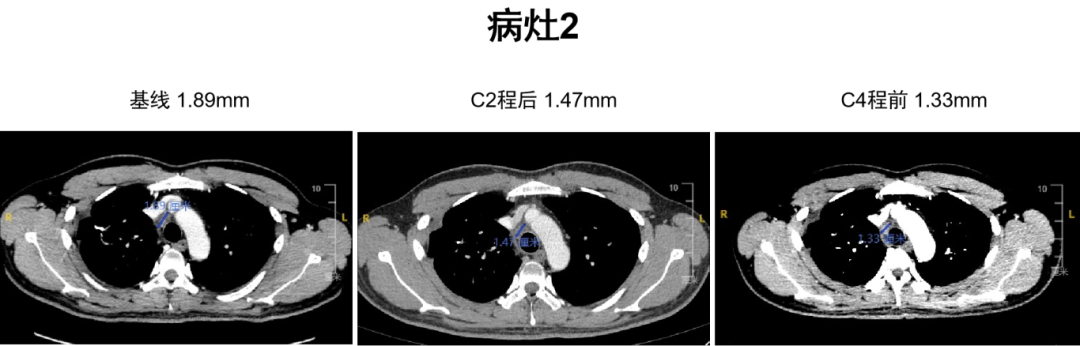

C2程后影像学评估为SD,C4程前为PR。

图片7.png

图4 病灶2影像学评估